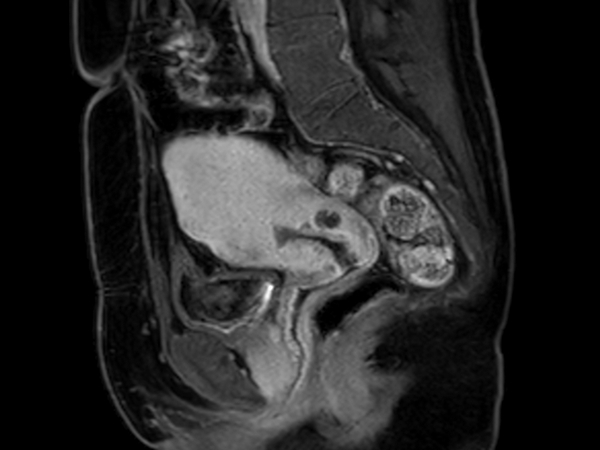

Sagittal MultiVane XD - T2w TSE